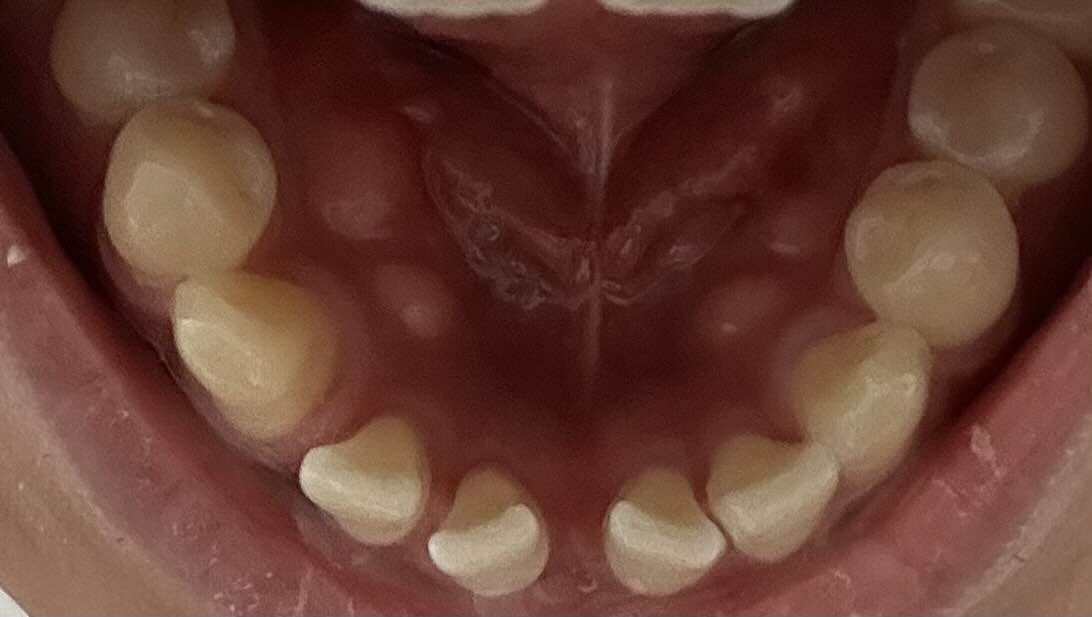

문정동 치과- 치아교정우선 제 이의 상태는 30대 남자, 앞니가 벌어진 모습이 보이고 약간의 부정교합이 있는 상태입니다. 아래 교정 전의 상태를 보여드리고 있구요. 이제부터 처음에는 일주일

우선 교정을 시작하기 전의 모습이에요. 앞니가 많이 벌어진 상태로 점점 조금씩 돌아가고 있는 모습이 정말 보기 싫었는데요. 사실 거울을 보면서도 크게 못 느꼈던게 사실이었기 때문에 아무 생각을 안하고 있었는데, 확실히 교정을 하고 나서 모습을 보니까 잘 한거 같아요.

9월 이전 교정 전 모습

확실히 교정기를 장착하기 전에 많이 벌어진 모습이 보여요. 특히 앞니는 조금씩 더 돌아가고 있어서 교정을 고민하던 중에 결정하게 된 이유기도 해요.